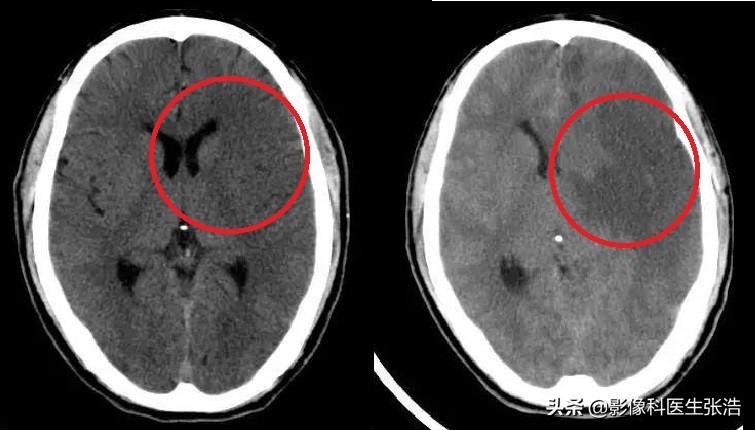

腦梗的診斷主要依據(jù)患者的病史、體格檢查和影像學(xué)檢查,醫(yī)生會根據(jù)患者的癥狀、體征以及可能的病因進行初步判斷,并結(jié)合頭顱CT、MRI等影像學(xué)檢查來確診。